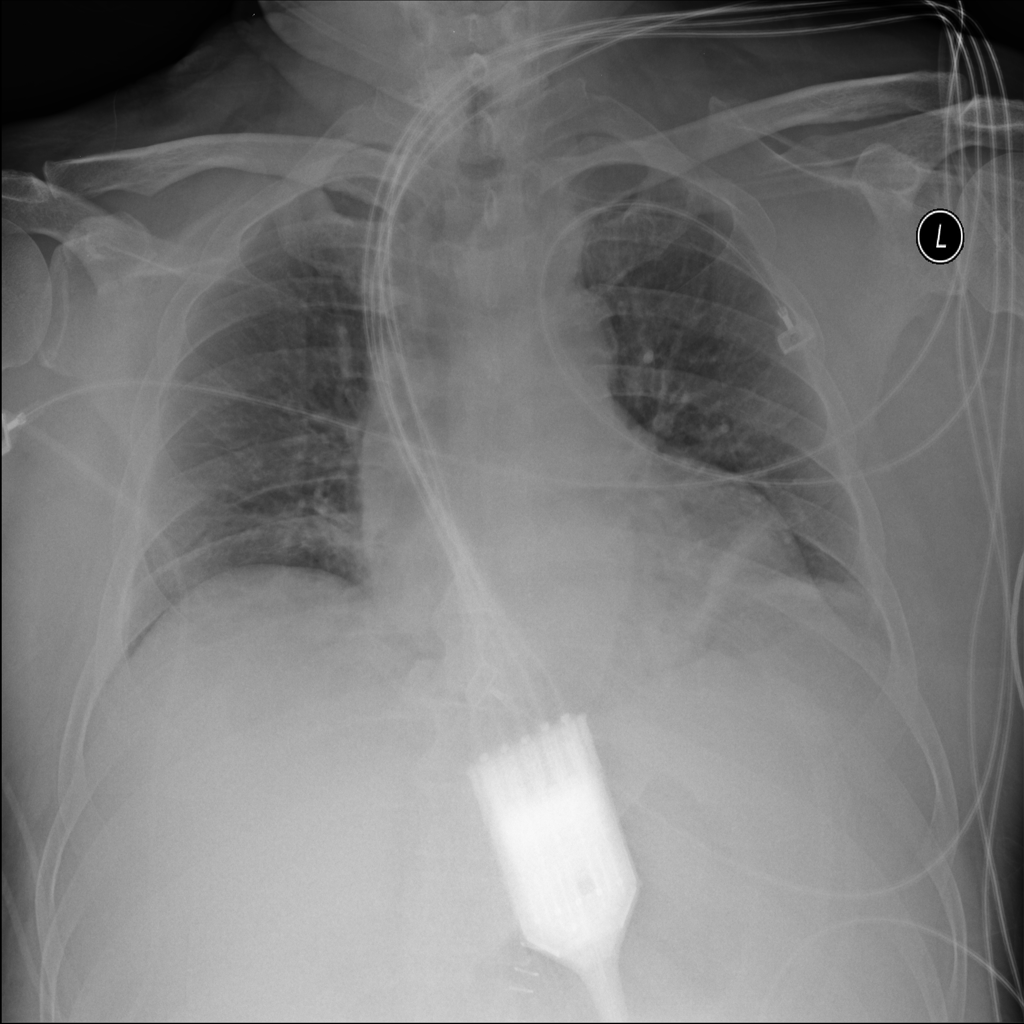

PAT-3384 · IMG-054Atelectasis

PAT-3384 · IMG-054

AP